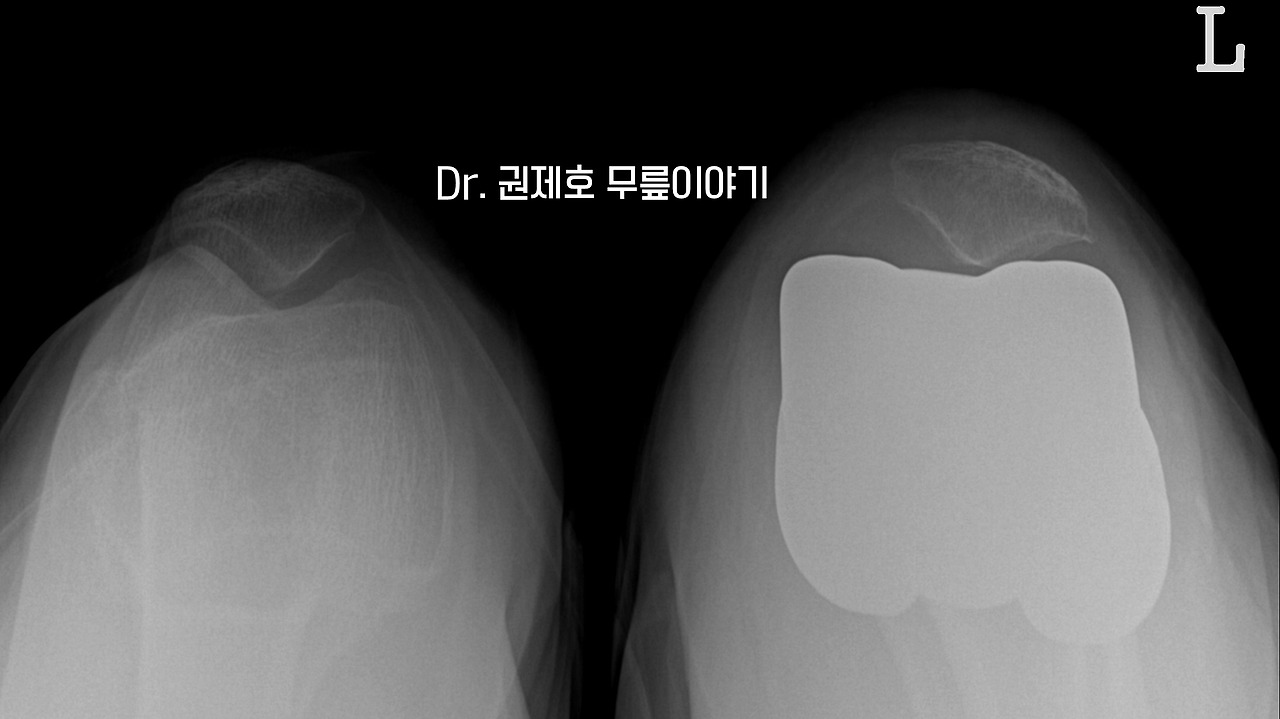

기존 무릎의 변화된 정렬을 다시 잘 맞췄는지 슬개골의 위치를 보고도 다시 확인한다.

관절염으로 휜다리가 있는 다리가 인공관절 후 반듯해진 모습을 확인할 수 있다.